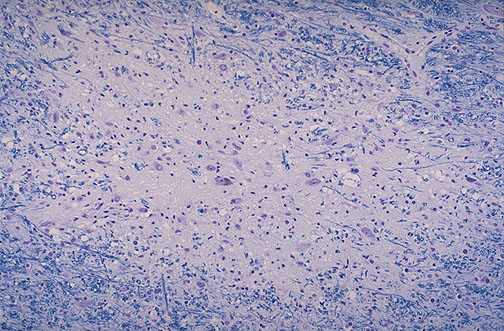

Progressive multifocal leukoencephalopathy (PML) affects oligodendrocytes, and cell lysis results in lesions that demonstrate demyelination, as shown here by the Luxol fast blue (LFB) stain in white matter.